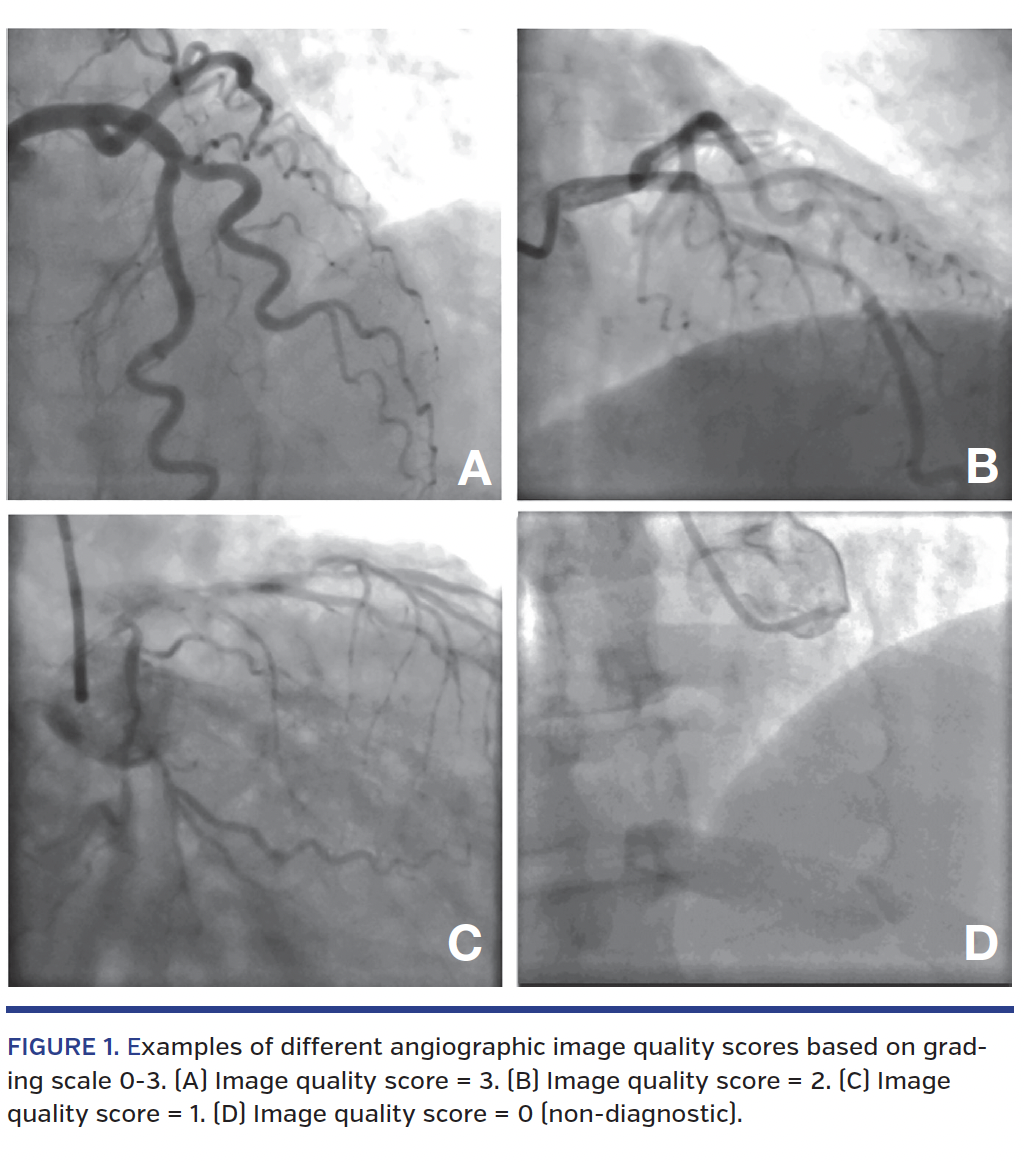

The primary endpoint for this study was the angiographic image quality. Four clinicians experienced in viewing CAGs were trained to analyze the image quality of each angiogram run based on a score of 0-3, using a scoring system adapted from a 2004 study by Reddy and colleagues,17 which designated 0 = picture non-diagnostic; 1 = moderate opacification of the vessel only in systole or diastole and the picture was diagnostic; 2 = complete opacification of the vessel but not throughout systole and diastole or moderate opacification of the vessel throughout systole and diastole; and 3 = complete opacification of the entire length of the vessel throughout systole and diastole (Figure 1).

Each patient was given an average score for the angiographic views of the LCA, and one for the RCA from each assessor. The final score was a mean of the four assessors’ scores. Each access site was also graded based on the proportion of images that were non-diagnostic (ie, score = 0) for clinical implication of the ability to produce diagnostic images. The assessors were told this was a quality assurance study only, and were thus blinded to the purpose of the study, because blinding to patient access site was not possible as it was apparent in the CAG images.